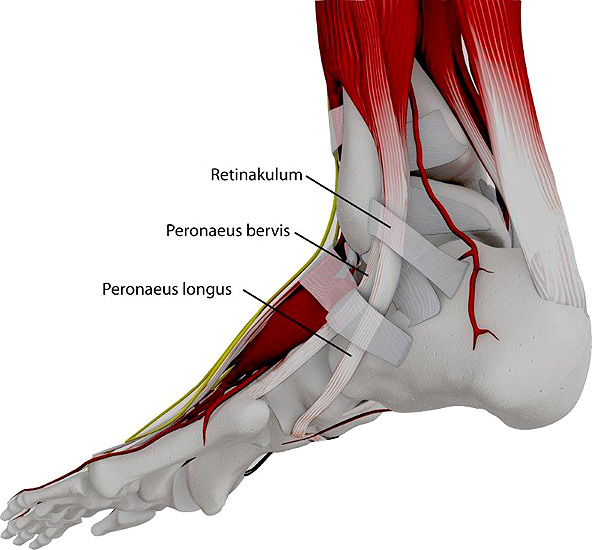

Die Peroneus brevis und die Peroneus longus Sehne verlaufen normalerweise hinter der Fibula (Abbildung 1). Neben der Gleitrinne an der Fibularückfläche sorgt das Retinaculum peroneale und das Retinaculum extensorum für eine weitere Stabilisierung. Bei der Peronealsehnenluxation oder –Instabilität können verschiedene Formen unterschieden werden (Abbildung 2):

Die Peronealsehnenluxation ist eine seltene Verletzung. Man unterscheidet akute und chronische Formen sowie eine vollständige und teilweise Luxation (Subluxation) 1234. Typischerweise ist die Peroneus longus Sehne betroffen. Diese luxiert nach ventral und lateral über die Fibulaspitze 1. Seltener tritt eine Luxation der Peroneus brevis Sehne auf. Von der Luxation muss die meist intratendinöse Peronealsehnenruptur und die Tendosynovialitis abgegrenzt werden. Als typischer Verletzungsmechanismus bei akuter Peronealsehnenluxation wird die plötzliche Anspannung der Peronealmuskulatur bei fixiertem Fuß genannt 12.

Etwa ein Drittel der Sehnenluxationen entsteht jedoch idiopathisch ohne adäquates Trauma. Als Ursache wird hier neben einer Schwäche des Retinaculums eine unzureichende Tiefe der Sehnenrinne an der hinteren Gelenkfläche der Fibulaspitze mit flacher Randleiste angenommen 567.